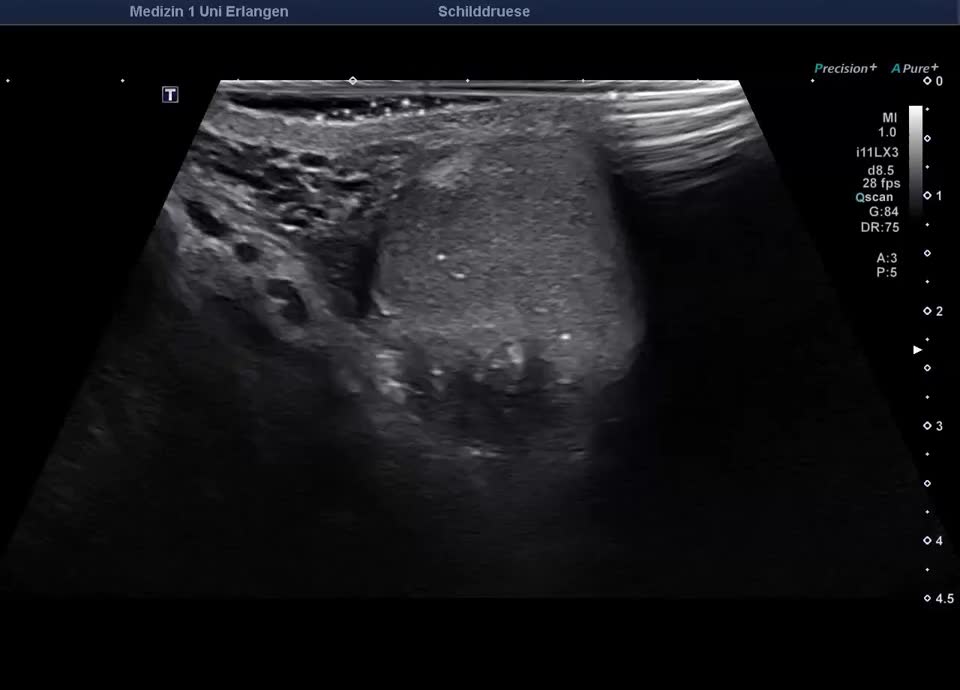

• Thyroid gland, Neck

• Autoimmune thyroiditis